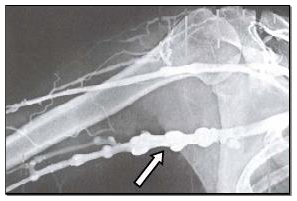

Observe a radiografia abaixo, que inclui a articulação do ombro, na porção indicada pela seta.

Observa-se pelo contraste, na porção indicada, um segmento de